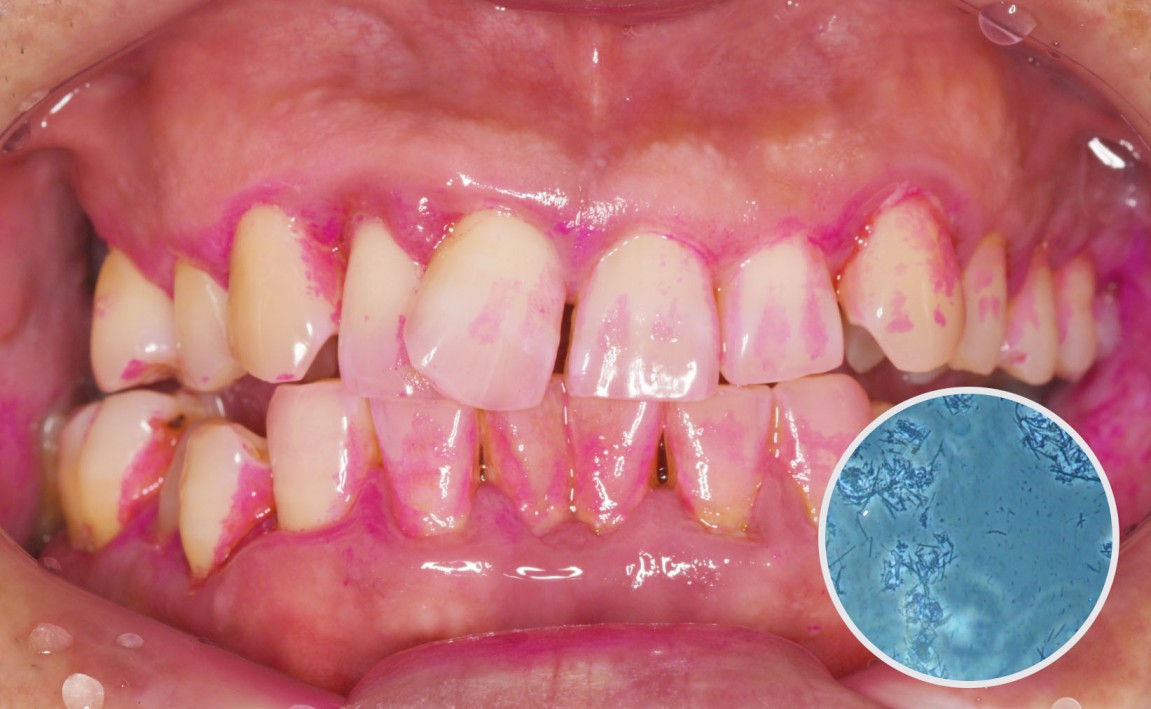

전.jpg

치료전 : 2024-06-24